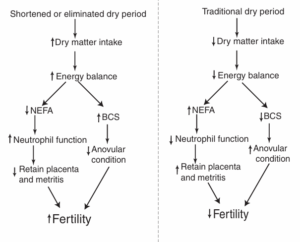

Fig 4: Model of the effect of shortening the dry period on fertility

Thus, shortening the dry period could be used as a management practice for achieving better reproduction in dairy cows.